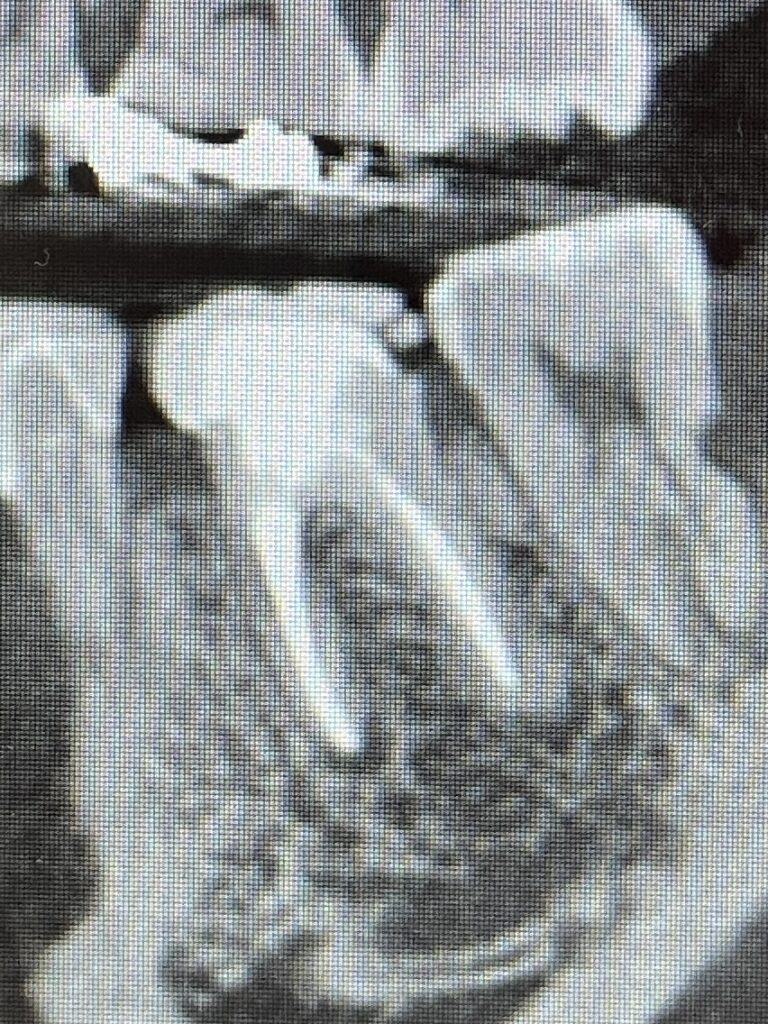

奥歯のやりかえです。真ん中に写っている左下奥歯(左側下顎第一大臼歯)の再治療です。神経治療からやり直しています。*色彩セラミックプラン